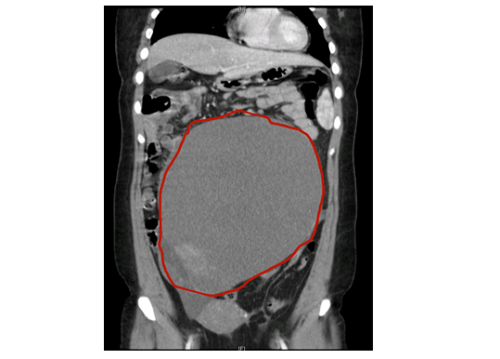

盆腔CT检查提示左侧卵巢巨大肿块大小约30CM

妇产科一区科主任、副主任医师黄佼介绍,患者阴式彩超及盆腔CT提示:盆腹腔巨大囊性肿块,大小约30cm,占据整个盆腹腔,结合其他检查结果考虑“左侧卵巢癌”。考虑到患者年轻,未生育,手术团队随后为患者行保留生育功能的卵巢癌全面分期术,所幸术后病检结果为左侧卵巢高分化粘液性囊腺癌IA期,无需进一步放化疗,患者术后恢复良好,出院后继续随访。